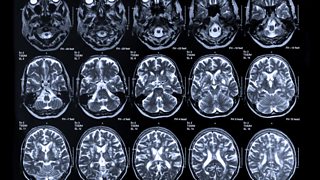

3. Brain Scans

Brain scans of people with more advanced Alzheimer's disease show clear damage to the brain. One of the first areas to be affected is often the hippocampus, deep within the brain, which is responsible for forming memories. Alzheimer's attacks the brain by causing proteins to make clumps, called amyloid plaques, and tangles which together block nerve cells, and spread to other parts of the brain, impairing language, understanding, facial recognition, movement and decision making.

Three types of brain scans are being used in the study to detect subtle changes in the brain much earlier. MRI (Magnetic Resonance Imaging) scans reveal the physical structure of the brain and show any shrinking to areas such as the hippocampus. PET (Positron Emission Tomography) scans use radioactive markers to show the position of amyloid plaques. MEG (Magnetoencephalography) scans show brain activity by measuring tiny changes in the brain's magnetic field.